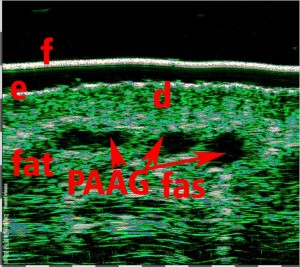

Εφαρμογές αισθητικής ιατρικής

-Έγχυση Πληρωτικών Υλικών (Fillers)